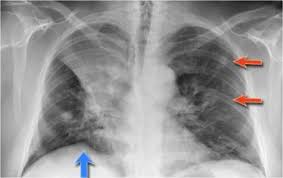

Mucus also contains antibodies which traps as well as destroys these invaders. Phlegm in the lungs traps and removes inhaled particles cellular debris and dead and aging cells. Atelectasis is often associated with chronic lung diseases such as copd asthma ards bronchiectasis or lung cancer. Lung and airway mucus traps dust bacteria viruses and other airborne particles then gets slowly propelled towards the throat by the cilia the tiny hairs that line the airways.

Mucus a slippery and sticky fluid found throughout the body plays an important role in the health of the respiratory system. If the mucous plug is in one of the smaller bronchial tubes the air behind the plug and the smallest airways called alveoli gets absorbed and this condition is called atelectasis. Mucus also acts as a trap for irritants like dust smoke or bacteria. Mucus plugs in the lungs generally develop in response to chronic underlying conditions of the respiratory or nervous system that weaken the lungs or surrounding muscles.